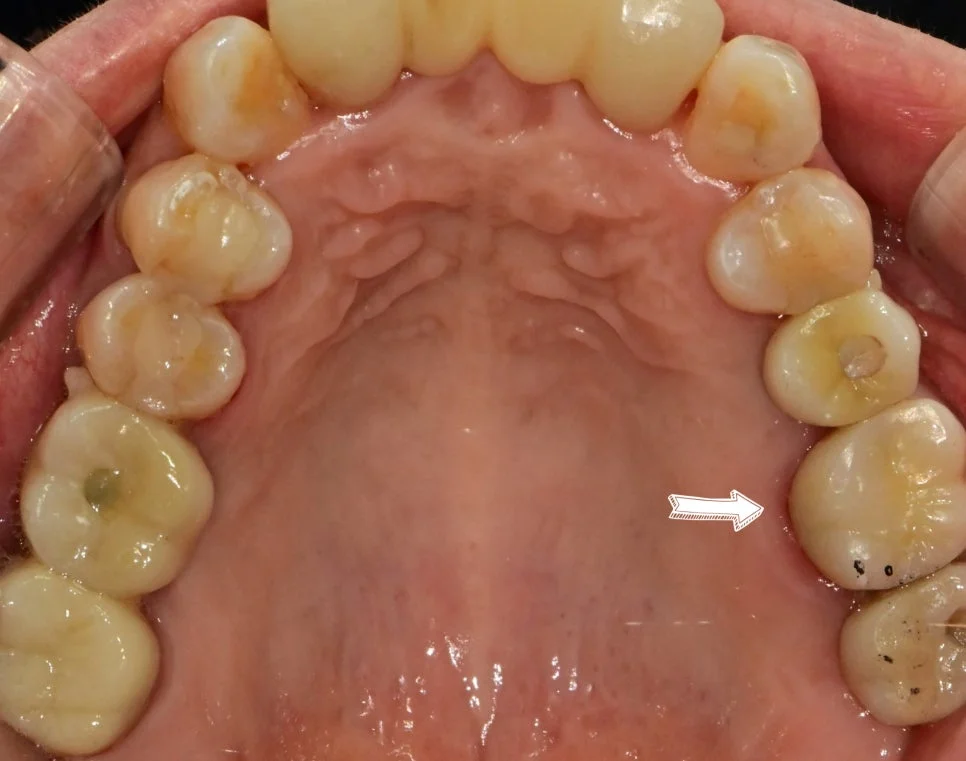

사례 3: 부적합 크라운 교체

왼쪽 위 어금니에 음식물이 많이 낀다는 말씀에 검진을 해보니 잘 맞지 않는 기존 크라운 하방에 상당한 음식물이 저류하고 있는데요.

부적합 기존 크라운 음식물 저류

기존 크라운 하방에 음식물이 고여 있는 상태

잘 맞지 않는 크라운 주변은 음식물이 쉽게 끼고, 그로 인해 냄새까지 발생할 수 있습니다.